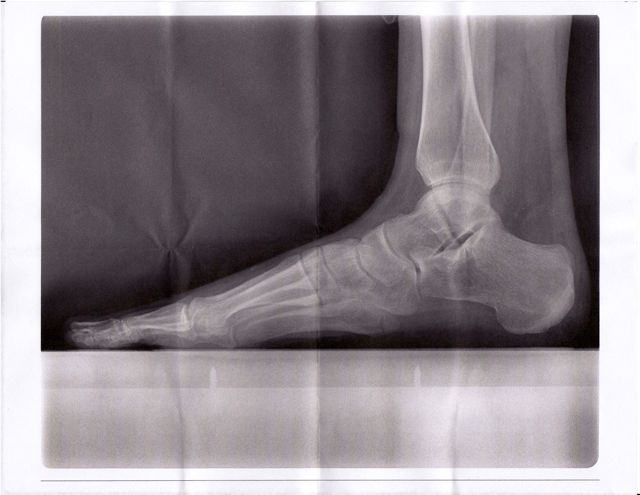

[Ok, so it’s hard to see with a low-res file, but…the bottom bone about 2/3 of the way across the page from left to right is the 5th metatarsal at the point of the fracture. See that line running up/across the light grey bone? That line that runs almost 3/4 of the way through the entire bone? Yeah. That’s not supposed to be there.]

I’m not sure I can describe the look on the doctor’s face today as he told me that I’d been walking around for 5 weeks with a 22 millimeter (about 2 cm) long fracture across the 5th metatarsal of my left foot…but it was basically something between shock and awe. “I’m a runner,” he said. “And you must be one tough woman to roll your ankle on top of a mountain and just keep on running.”

“I understand that,” he told me, shaking his head. “But…wow.” He tapped the end of his pen on the the XRay. “You’re lucky,” he said. “Most athletes with this injury get it higher up on the metatarsal. It’s called the ‘Jones fracture’ and it requires surgery for most folks. Your fracture has already started healing.”